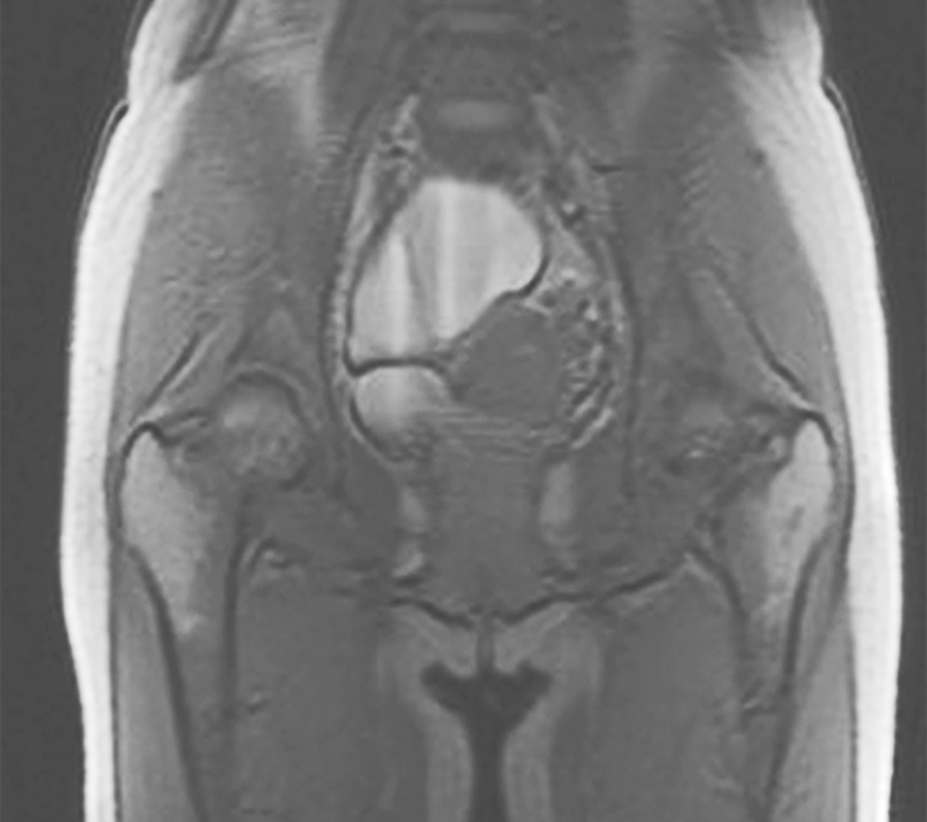

女性盆腔超声、MRI及男性睾丸超声有助于协助明确性腺有无形态学异常。如图2所示为北京协和医院诊治的1例女性FGAs的盆腔MRI,可见巨大卵巢囊肿;图3所示为北京协和医院诊治的1例女性FGAs的盆腔超声,可见多发卵巢囊肿。

图2 1例女性垂体FGA盆腔MRI提示卵巢囊肿